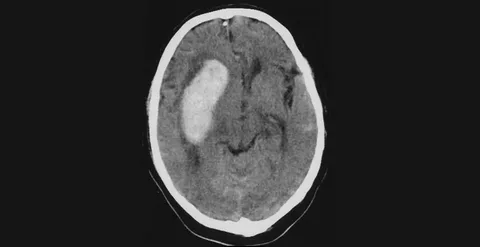

Представьте: вы чувствуете лёгкое головокружение, «мушки» перед глазами, временами немеет рука… Но списываете всё на усталость, стресс или возраст. А между тем в сосудах шеи — тех самых, что питают мозг, — уже идёт процесс, который может привести к инсульту. И это не преувеличение. Сосуды шеи — особенно сонные и позвоночные артерии — играют ключевую роль в кровоснабжении головного мозга. Через них проходит до 80% крови, идущей к мозгу. Если в этих сосудах появляются бляшки, сужения или нарушается кровоток — мозг начинает «голодать». Сначала тихо, потом — резко и без предупреждения. Хорошая новость: инсульт часто можно предотвратить. И один из самых простых, безопасных и информативных способов — УЗИ сосудов шеи (дуплексное сканирование). Это не больно, не требует подготовки, занимает 15–20 минут и показывает состояние сосудов в реальном времени. Но когда именно стоит его делать? Не ждать же первого удара! Разберёмся, какие сигналы подаёт тело — и почему в некоторых случаях УЗИ становитс

Почему инсультов больше при умеренно высоком давлении 140–160, чем при очень высоком 180–200 и выше? Интуитивно ведь ожидается обратное, однако данные, основанные на больших выборках, показывают иную картину. Дело в том, что риск инсульта растет непрерывно с повышением уровня артериального давления, причем без какого-либо порогового уровня, за которым начинался бы скачкообразный рост. При этом людей с показателями 140–160 мм многократно больше, чем с АД 180–200 мм, поэтому именно в таком диапазоне умеренно повышенного давления накапливается большее абсолютное число этих тяжких событий - инсультов. Важнейшую роль играет и длительность экспозиции. Давление около 150 часто сохраняется годами и приводит к хроническому повреждению сосудистой стенки, ремоделированию артерий и ускорению развития атеросклероза. Очень высокие значения вроде 190 мм обычно длятся куда как меньше, довольно часто сопровождаются симптомами, приводят к обращению за медицинской помощью и мотивируют к более тщательн